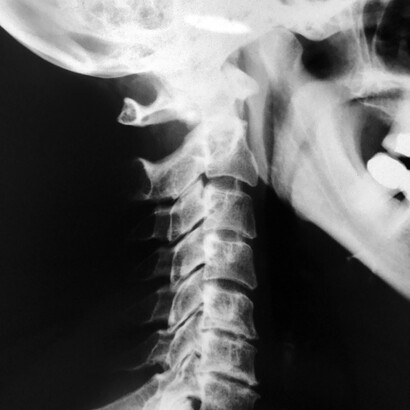

Las vértebras cervicales son 7 y están involucradas en la flexión, rotación, inclinación y extensión de la cabeza. Y lo hacen miles de veces al día, con lo que podemos hacernos una idea de que un simple desajuste puede desencadenar un bloqueo o dolor fácilmente.

Los discos cervicales son los cojines entre las vértebras en la parte superior de la espalda y el cuello. La hernia del disco tiene lugar cuando el núcleo gelatinoso del disco interno, el núcleo pulposo, se rompe o hernia, a través de la pared externa del disco cervical.

Se manifiesta de diversas formas, por ejemplo, es posible que irradie dolor del brazo hacia la mano o los dedos. También podemos sentir entumecimiento o debilidad en la zona de los hombros, brazos y manos.